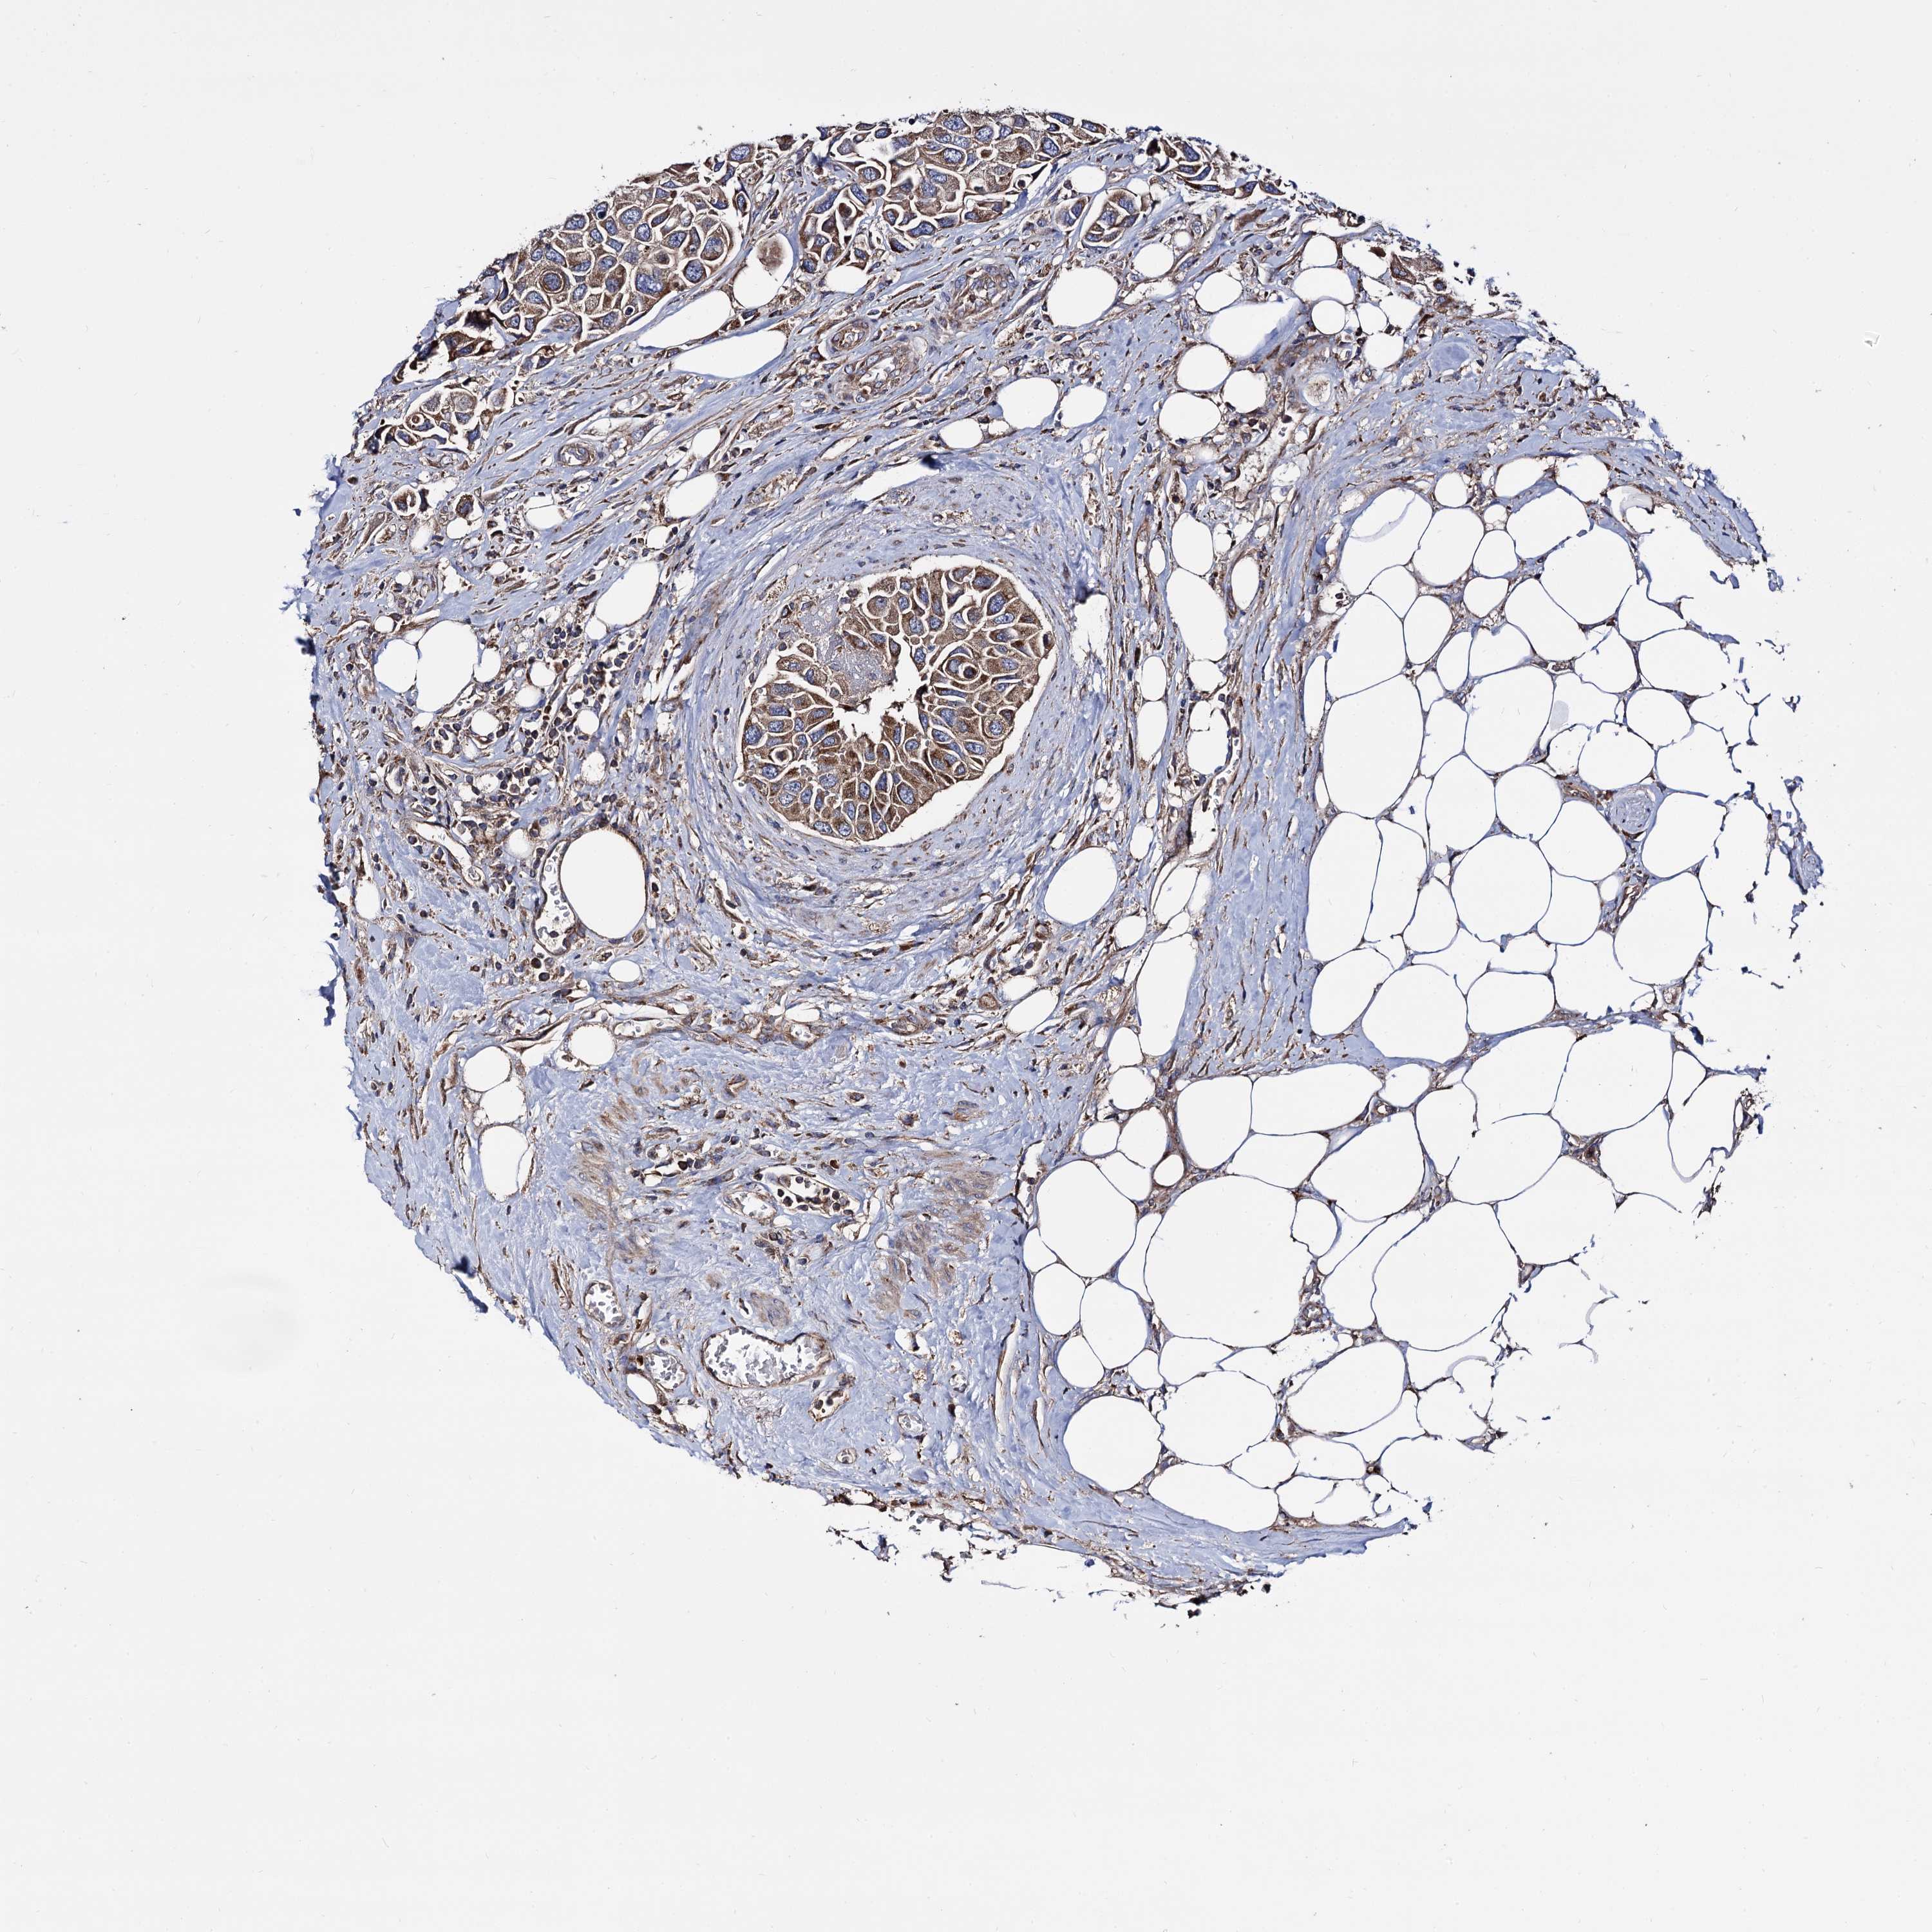

UROTHELIAL CANCER - Protein expressioni

A mouse-over function shows sample information and annotation data. Click on an image to view it in a full screen mode. Samples can be filtered based on level of antibody staining by selecting one or several of the following categories: high, medium, low and not detected. The assay and annotation is described here.

Note that samples used for immunohistochemistry by the Human Protein Atlas do not correspond to samples in the TCGA dataset.

Antibody stainingi

Antibody staining in the annotated cell types in the current human tissue is reported as not detected, low, medium, or high, based on conventional immunohistochemistry profiling in selected tissues. This score is based on the combination of the staining intensity and fraction of stained cells.

Each image is clickable and will lead to virtual microscopy that enables deeper exploration of all samples and also displays staining intensity scores, fraction scores and subcellular localization as well as patient and tissue information for each sample.

Antibody HPA040845

Staining

High

Medium

Low

Not detected

Intensity

Strong

Moderate

Weak

Negative

Quantity

>75%

75%-25%

<25%

None

Location

Nuclear

Cytoplasmic/membranous

Cytoplasmic/membranous,nuclear

Urothelial carcinoma, Low grade